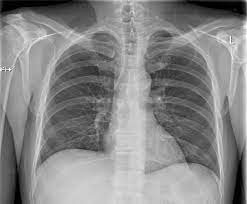

Interpretation of the chest x ray. Chest x ray is probably the most common imaging test. In addition to text and pictures, this tutorial contains interactive features which supplement the text and make it a more dynamic learning. Examination of the chest x ray is a process which requires a systematic approach. Standard frontal chest radiograph (roentgenogram) — upright; Recognizing normal anatomy on the cxr is key to understanding and interpreting abnormalities. Few providers (including mds) are comfortable interpreting their own films. In fact every radiologst should be an expert in chest film reading. Normal heart size is half of the chest width. Generally speaking, a normal cxr should have the lungs looking like zebras in that they are all black with strips. The aim of this study was to investigate the diagnostic accuracy of cxr interpretation by reporting radiographers (technologists). The chest radiograph remains the most important method of chest imaging, providing an easily accessible, inexpensive, quick, and effective diagnostic tool. Learn about chest x ray interpretation with free interactive flashcards.

Normal heart size is half of the chest width. Standard frontal chest radiograph (roentgenogram) — upright; In fact every radiologst should be an expert in chest film reading. Generally speaking, a normal cxr should have the lungs looking like zebras in that they are all black with strips. These images were saved with anonymous biodata for iom radiology collection and teaching purposes.